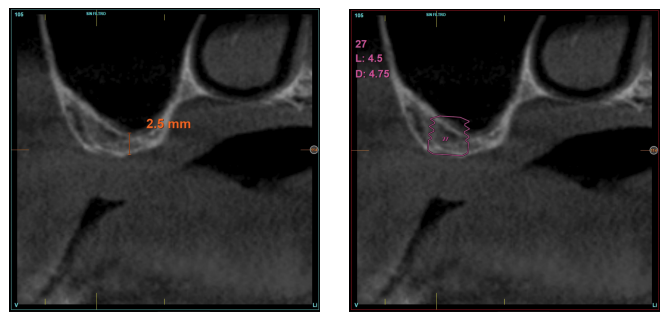

En todos los casos, se realizó un diagnóstico basado en modelos de estudio, exploración intraoral del paciente y realización de un Cone-beam analizado mediante el software específico BTI-Scan III (Biotechnology Institute, Vitoria, Alava, España).

La altura media del volumen óseo residual fue de 3,1 mm (+/- 0,3 mm con un rango de 3-4 mm). En todos los casos se realizó una elevación de seno transcrestal, con hueso autólogo particulado obtenido del fresado de la zona de generación del neoalveolo para la inserción del implante, siendo la media de esta elevación sobre el ápice del implante en milímetros de 2,8 mm (+/- 0,99 rango 1,9 -5 mm). En el TAC de control al año de carga de los implantes estudiados, se mantiene la ganancia ósea lograda, no observándose disminución del volumen ganado, únicamente tres casos mostraron una disminución de entre 0,4 y 0,5 mm del volumen inicial al final (Tabla).

En las Figuras 2- 19 se muestra uno de los casos incluidos en el estudio.

en altura de 3,4 mm, siendo más uniforme en esta ocasión en toda la zona de la cresta. Se planifica un implante de 4,5 mm de longitud y

4,75 mm de diámetro.